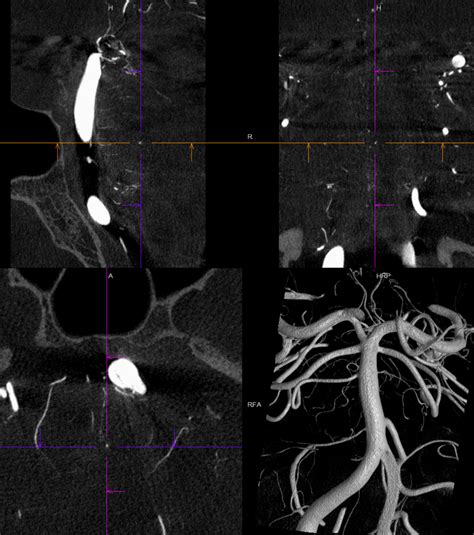

• Computed Tomography (CT) Scan: A CT scan can detect bleeding in the brain, which may indicate a ruptured aneurysm.

• Magnetic Resonance Imaging (MRI): An MRI can provide detailed images of the brain and may reveal the presence of an aneurysm.

• Angiography: This procedure involves injecting a contrast dye into the blood vessels and using X-rays to visualize the blood flow. It can help identify the location and size of the aneurysm.

Given the microscopic nature of Charcot Bouchard aneurysms, a combination of these diagnostic tools is often necessary to confirm the presence of the condition.